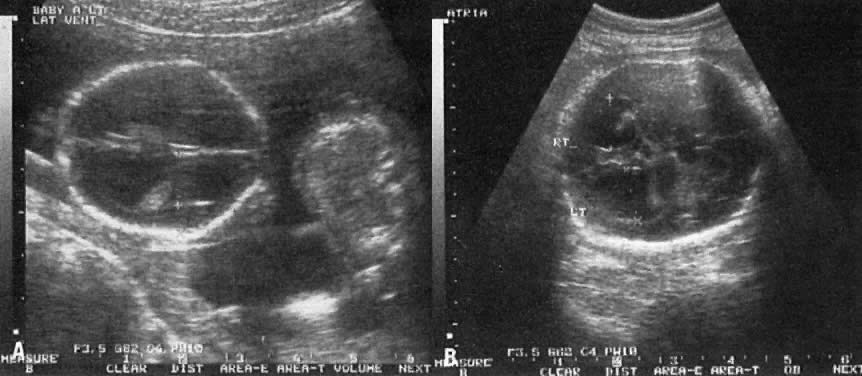

Hydrocephaly

Figure 22 depicts the flow of CSF in hydrocephaly. Any lesion preventing normal flow of CSF from the lateral ventricles to the cisterns results in hydrocephaly.

Obstruction at the level of the aqueduct of Sylvius results in enlargement of the third and lateral ventricles (Fig. 23). The etiology of such obstruction includes (1) X-linked recessive inheritance, (2) infection with cytomegalovirus or toxoplasmosis, and (3) other lesions that impinge on the area.

Fig. 23. A. Head echogram of a fetus with hydrocephalus and dilation of the lateral ventricle. The ratio between the distance from the midline to (1) ventricular wall (+), and (2) inner aspect of the parietal bone(x) is used to assess severity of the condition. In this fetus, the ratio is 67% (normal is approximately 35%) . Note compression of the choroid plexus adjacent tot he ventricular wall and to the left of the + sign. B. Head echogram of fetus with hydrocephalus, showing dilation of the ventricular atria (+ and X, respectively). Each atrium measures 2.3 cm (normal, 0.2 to 1.0 cm)

In contrast to simple ventriculomegaly, hydrocephalus usually is more progressive, and it is frequently associated with compression of the choroid plexus (see Fig. 23).

The progression of hydrocephalus may be gauged by (1) the ventricular:hemispheric ratio, and (2) the diameter of the ventricular atrium (see Fig. 22 and Fig. 23).66, ,68 Dilation of the ventricular atrium is also a characteristic finding in agenesis of the corpus callosum. In such cases, the third ventricle is displaced cephalad and the frontal horns laterally.69